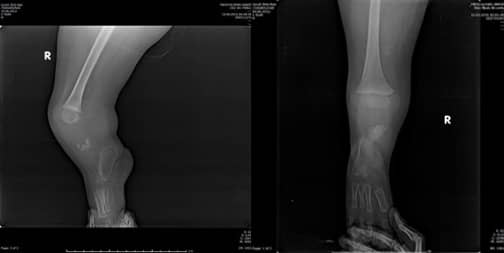

Когато пациентът дойде при нас за контрол осем години по-късно, беше установено, че изпитва болка поради костно израстъче в задно-страничната част на крузиса, валгусна деформация и липса на приблизително 25-градусово разгъване в коляното (Фиг. 7. А, В.).

Фиг. 7: А: Сагитален изглед

B: Коронален изглед

Обхватът на сгъване беше почти пълен. В резултат на това беше препоръчана операция за корекция на механичната ос, за да се постигне почти пълно разгъване на коляното и за отстраняване на костното израстъче, което притиска протезата. Планирана беше отворена клиновидна остеотомия с цел предотвратяване на скъсяване на остатъка на крузиса, според рентгеновото изследване на пациента.

Преоперативни изображения, показващи валгусната и флексионната деформации на засегнатия крак (Фиг. 8 А, В).

Фиг. 8: Преоперативни изображения, показващи

А. Валгусна деформация

В. 25-градусова контрактура на флексият